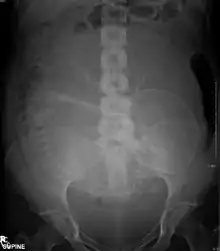

| Abdominal | 0.1 - 3.0[1] |

| Lumbar spine | 1.0 - 10[1] |